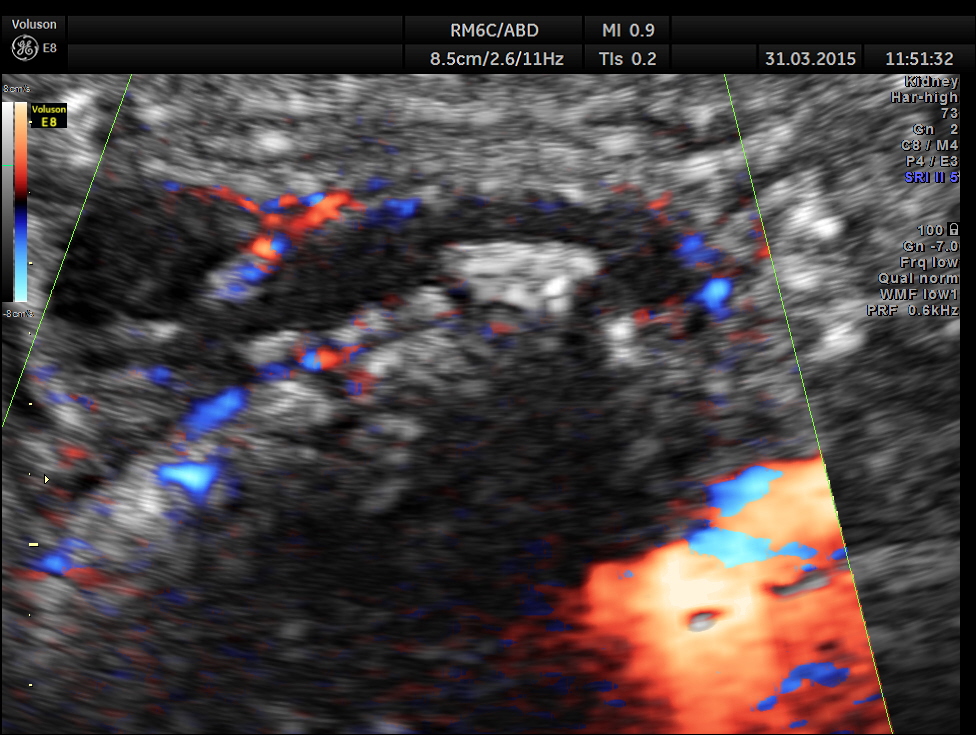

Ultrasound showed the following.

Right kidney shows mild pelvi calyceal dilatation.

Scan ( with a regular abdominal probe ) over RIF shows an echogenic object with posterior acoustic shadowing within a dilated ” tube ” .

Can we jump to the diagnosis of ureteric calculus now ?

Is there an incongruity between the size of the calculus and the ” ureteric dilatation ” and the pelvi calyceal dilatation ?

Colour Doppler shows vascularity of the wall . It was non pulsatile and non collapsible.